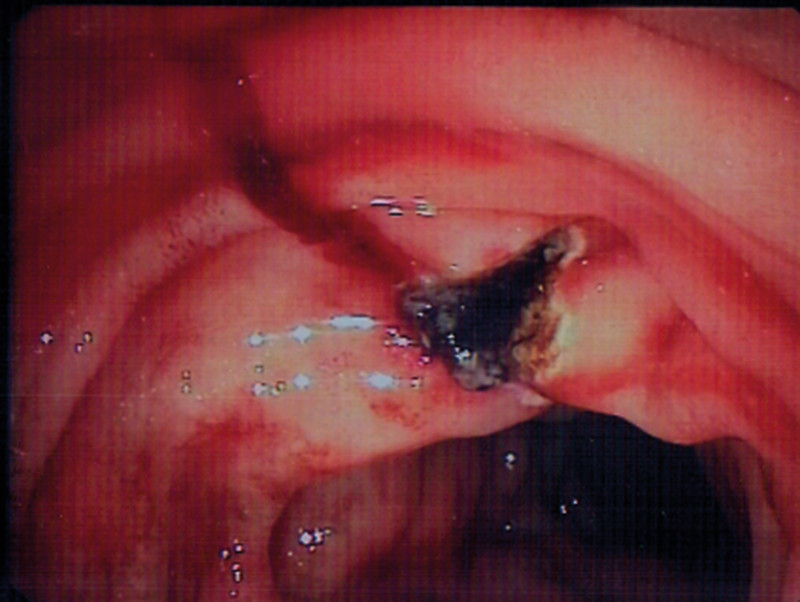

Pasientens hemoglobinnivå var stabilt på 7,7 g/100 ml til dagen etter (dag 3) og fortsatte å stige utover dagen (8,4 g/100 ml) uten ny tilførsel av blod. Det var ingen avføring/melena morgen/ettermiddag. Ny gastroskopi (nr. 4) bekreftet at blødningen var stanset (fig 3). På grunn av opplysninger i sykehistorien om mulig lettgradig hemoragisk diatese ble det konferert med hematolog, som anbefalte å ta von Willebrand-prøver i rolig fase. Det ble også konferert med revmatolog, som ikke fant holdepunkter for vaskulitt. En CT-undersøkelse av abdomen avdekket kun lett ødem i duodenalveggen.